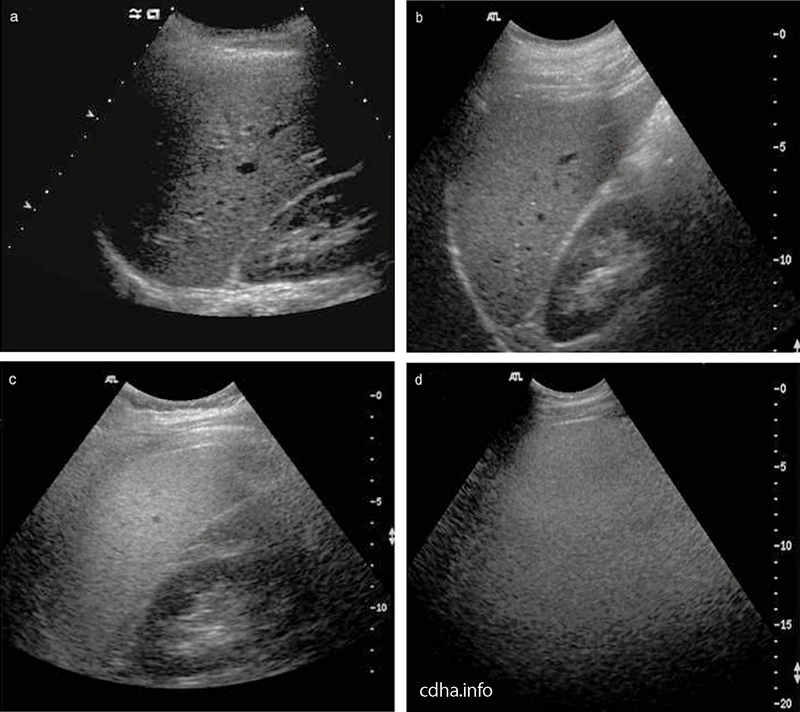

Siêu âm ổ bụng là phương pháp chẩn đoán hình ảnh sử dụng sóng siêu âm để quan sát các cơ quan nằm trong vùng bụng, bao gồm gan, túi mật, tụy, thận, bàng quang và một phần của ruột. Đây là kỹ thuật không xâm lấn, không gây đau, không sử dụng tia X và có thể thực hiện nhiều lần mà không gây ảnh hưởng đến sức khỏe.

Siêu âm giúp đánh giá kích thước, cấu trúc và mật độ gan, phát hiện sớm các bất thường như gan nhiễm mỡ, xơ gan, u gan, nang gan hoặc áp xe gan. Đây là cơ quan dễ bị tổn thương do lối sống ít vận động, sử dụng rượu bia hoặc viêm gan virus.

Siêu âm thận giúp phát hiện sớm sỏi thận, thận ứ nước, viêm thận, nang thận hoặc các khối u. Đây là kỹ thuật cần thiết cho những người có tiền sử tăng huyết áp, tiểu đường hoặc từng bị nhiễm trùng tiết niệu.